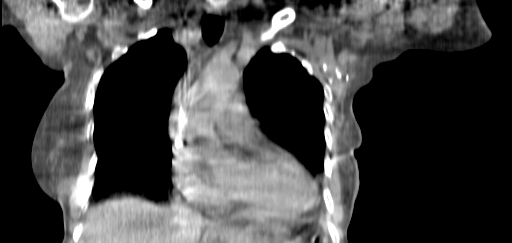

Planning CT Images

ClearRT® Images